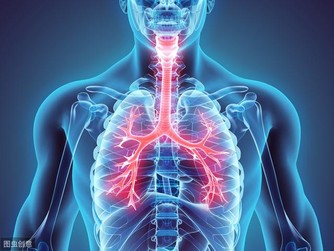

這是由於肝臟本身就有強大的代謝功能,肝癌的表現多種多樣,容易被忽視。肝位於上腹部,肝癌初期並無徵兆,一般人難以察覺,甚至當腫瘤增大至十公分以上時,有的人還是缺乏典型症狀。

當肝臟腫瘤逐步增大,有可能會壓迫附近的橫膈膜,亦可壓著肺部以下的肌肉神經。而這些被壓著的神經正好是連接右肩的神經,就會引發右肩疼痛。所以,當出現反反复复的右肩膀疼痛時,經過適當的治療,症狀未能好轉,要及時檢查肝臟以排除存在的病變。